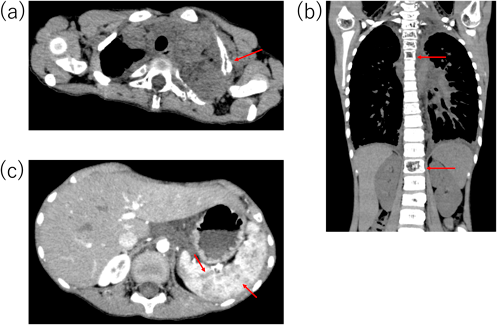

今後の治療方針を検討していたところ,心臓カテーテル検査後6カ月後頃から徐々に肋骨の突出が目立つようになり,圧痛も認めるようになった.造影CT検査を再検したところ,左第1・2肋骨の骨皮質欠損・骨溶解像(Fig. 4a)に加え,椎体の骨折(Fig. 4b),脾臓に多数の嚢胞状造影不良域(Fig. 4c)を認めた.特徴的な画像所見を有し,これまでの臨床経過と合わせてGLA/GSDの診断に至った.現在シロリムス内服治療を開始し約2年経過しているが,骨皮質は改善傾向で症状の増悪は認めていない.

Pediatric Cardiology and Cardiac Surgery 42(1): 15-20 (2026)

Fig. 4 Chest and abdominal enhanced CT

(a) Red arrow shows cortical bone defects and osteolysis of the rib. (b) Red arrows show fracture of the vertebral bodies. (c) Red arrows show numerous cystic poor contrast lesions in the spleen. CT, computed tomography